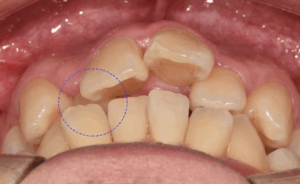

안녕하십니까, 망우역 치과 글로리 김정은 대표원장입니다. 『아름다운 미소에서 예쁜 치열은 필수 요소인데요.』 오늘은 전치부 재배열 후 아름다운 미소를 되찾은 사례의 치료 과정에 대해 설명해 드리도록 하겠습니다. 『1. 틀어진 앞니 교정』…